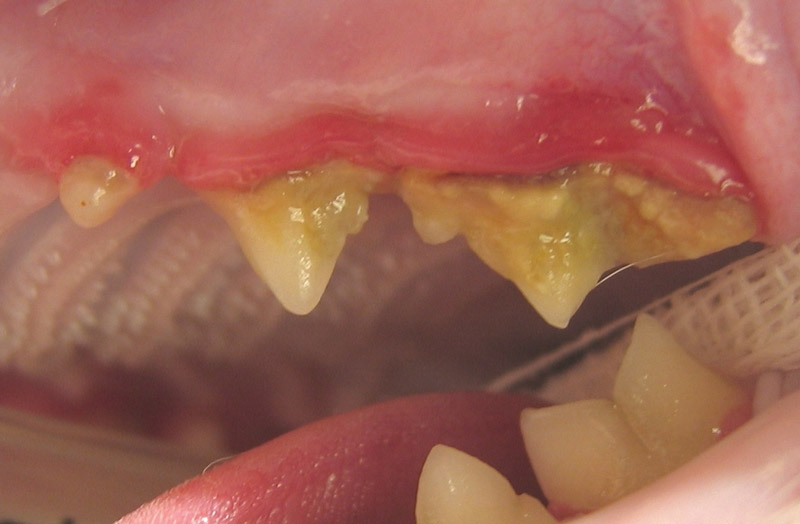

Raziskave kažejo, da se parodontalna bolezen – skupni izraz za različna vnetja v ustni votlini - pojavlja pri 70 % mačk še preden dopolnijo 3 leta*. Simptome parodontalne bolezni je težko zaznati, zato ni nujno, da boste opazili kakršnekoli znake pri svoji mački. Če parodontalne bolezni ne zdravimo, pride do hude bolečine v ustni votlini, prav tako pa se lahko bakterije razširijo po celotnem telesu. To pomeni, da je skrb za higieno zob in dlesni temeljnega pomena. Na voljo so enostavni koraki, ki vam lahko pomagajo, da svoji mački zagotovite ustrezno higieno zob in dlesni in se s tem izognete morebitnemu nelagodju in bolečinam. Za več informacij se obrnite na svojega veterinarja.